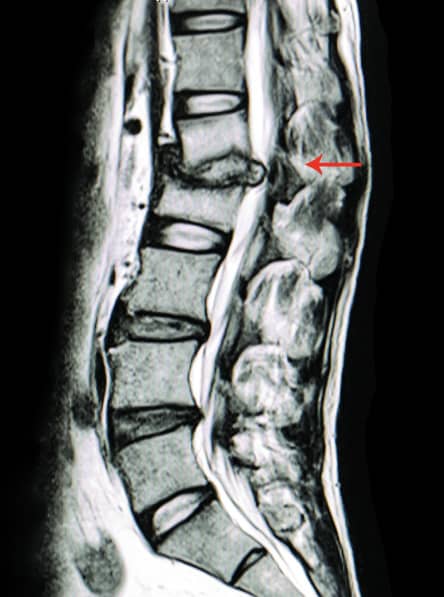

Uso de radiografías y resonancia magnética

Las radiografías son útiles para detectar problemas estructurales de la columna, como cambios degenerativos o malformaciones. La resonancia magnética (RM) proporciona imágenes detalladas de los tejidos blandos y puede revelar:

- Hernias de disco.

- Estenosis raquídea.

- Compresiones nerviosas en la región lumbar.